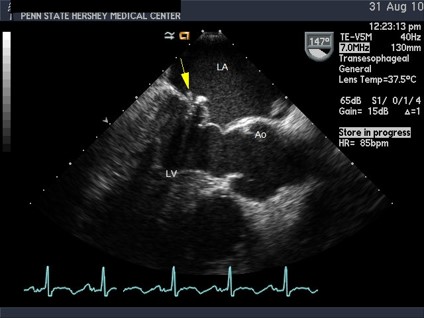

The TEE shows a small, oscillating (mobile) vegetation on the mitral valve with a small adjacent leaflet perforation but no abscesses. It is otherwise similar to the transthoracic study.

A still frame of anterior leaflet mitral valve prolapse in a transesophageal long-axis view.